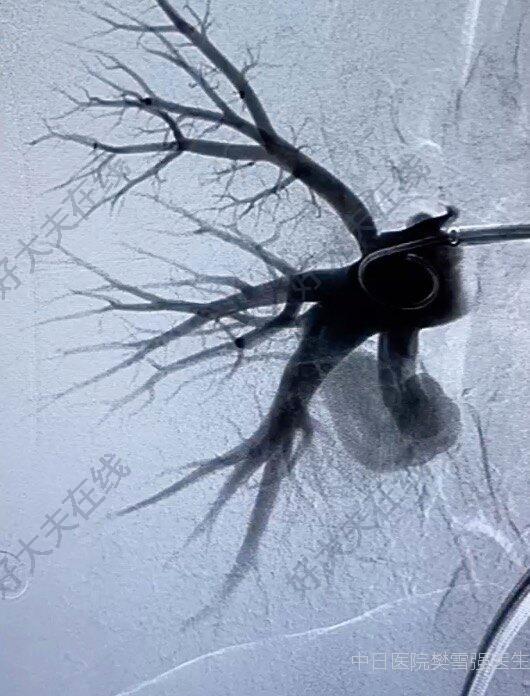

病情簡介患者,老年女性,因間斷腹脹、腹痛半年余,加重2月余入院;1月余前出現(xiàn)自發(fā)性腹膜炎,保守治療后好轉(zhuǎn);無消化道出血病史;慢性腎功能不全尿毒癥期,透析1年余;Child-pugh評分8分,B級;MELD評分23分。手術(shù)過程肝動脈顯影后,門靜脈提早顯影查找可疑瘺口栓塞完成后,肝動脈期未見門靜脈顯影隨訪結(jié)果加強(qiáng)透析1月后(由每周2次改為每周3次),復(fù)查CT見腹水消退文獻(xiàn)速遞肝動脈-門靜脈瘺是指肝動脈與門靜脈之間存在異常通道,可源于先天性血管發(fā)育異常,也可繼發(fā)于創(chuàng)傷、肝癌、醫(yī)源性肝損傷(肝組織活檢、經(jīng)皮經(jīng)肝膽管引流術(shù)等)。Guzman等將肝動脈-門靜脈瘺分為3類:無癥狀的小的肝動脈-門靜脈瘺無需特殊處理;如導(dǎo)致門脈高壓合并食管胃底靜脈曲張破裂出血或大量胸腹腔積液,則需要積極處理。介入栓塞可取得較好效果,如栓塞失敗,也可考慮手術(shù)治療如肝動脈結(jié)扎或瘺口切除等,但手術(shù)創(chuàng)傷較大,現(xiàn)已少用。也有TIPS治療肝動脈-門靜脈瘺的報(bào)道,Kakati等報(bào)道了一例栓塞術(shù)后3天復(fù)發(fā)黑便,行TIPS治療的病例。參考文獻(xiàn)[1]?GuzmanEA,McCahillLE,RogersFB.Arterioportalfistulas:introductionofanovelclassificationwiththerapeuticimplications.JGastrointestSurg.2006Apr;10(4):543-50.doi:10.1016/j.gassur.2005.06.022.PMID:16627220.[2]?KakatiBR,PedersenMR,ChenSY,HirschKS,BerggreenPJ,SeetharamAB.Hepaticarterioportalfistulapresentingasgastricvaricealhemorrhage.JGastrointestinLiverDis.2014Jun;23(2):211-4.doi:10.15403/jgld.2014.1121.232.brk1.PMID:24949615.術(shù)者:葉志東樊雪強(qiáng)張建彬許欽琦